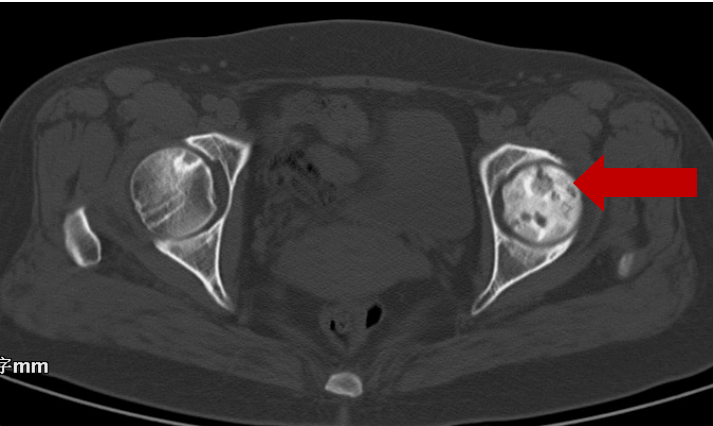

2008年10月21日CT显示:

右股骨头坏死二期

2021年05月20日末次复查CT显示:

右股骨头坏死三期,左股骨头正常